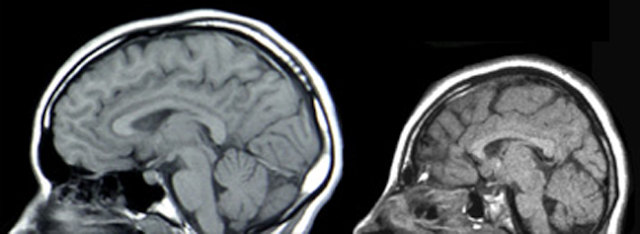

hoặc hội chứng đặc hiệu. Chụp cộng hưởng từ (MRI) có thể cần thiết trong một số

tình huống nhất định định để hỗ trợ xác định nguyên nhân gây ra tật đầu nhỏ.